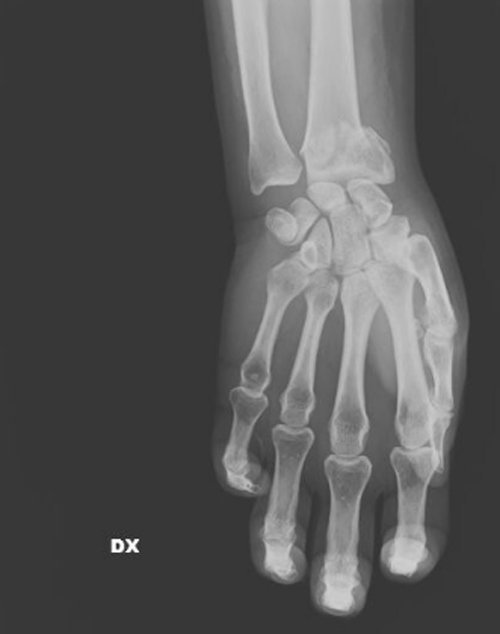

Σπασμένος καρπός

Όπως σημειώνει η χειρουργός, καθημερινά καλούνται να αντιμετωπίσουν «σπασμένα οστά σε μύτη, χέρια, πόδια, πληγές από μαχαιριές, εγκαύματα, μελανιές και άλλα σημάδια στραγγαλισμού», ενώ σημειώνει πως έχει δεχθεί ασθενή ακόμη και με μαχαίρι στην πλάτη, που όμως το περιστατικό δηλώθηκε ως «ατύχημα» στο νοσοκομείο.

Σύμφωνα με την Βανταντόρι, στις ακτινογραφίες αντικατοπτρίζεται η καθημερινή φρίκη που αντιμετωπίζει με τους συναδέλφους της στα «Επείγοντα». «Συχνά οι τραυματισμένες γυναίκες δεν έχουν τη δύναμη να πουν τι τους έχει συμβεί, αλλά τα σώματά τους και τα τραύματά τους μιλούν από μόνα τους», σημειώνει.

«Όλα αυτά τα χρόνια έχω δει χιλιάδες ακτινογραφίες γυναικών με κάθε είδους τραύματα, ακόμη και πολύ σοβαρά. Πολλές από αυτές τις κακοποιημένες γυναίκες αρνήθηκαν ότι τα τραύματά τους προκλήθηκαν από τους συζύγους ή άλλα μέλη της οικογένειάς τους. Η άρνησή τους σχετίζεται με συναισθήματα όπως φόβος, ντροπή, αγωνία για την τύχη των παιδιών τους ή και για τη ζωή τους ακόμη», σημειώνει η γιατρός.